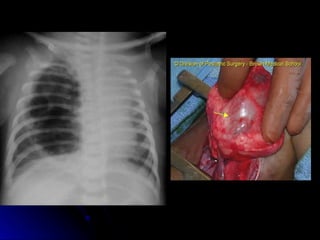

Congenital lobar emphysema

 Lesions that cause air trapping, with

Lesions that cause air trapping, with

compression of surrounding tissue

 Most common in left upper, right middle

Most common in left upper, right middle

and right upper lobes

 Usually attempt low volume ventilation.

Usually attempt low volume ventilation.

Sometimes selective intubation of other

bronchus

 May require surgical resection

May require surgical resection